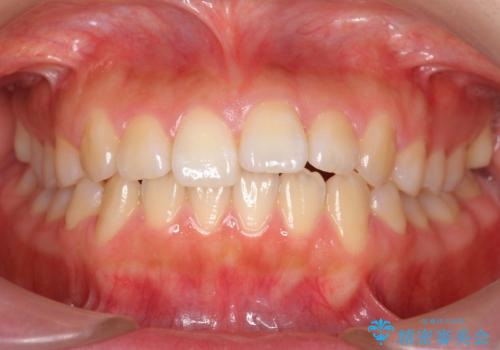

20代女性 八重歯 奥歯の反対咬合 前歯のがたがた 急速拡大装置で

- 八重歯を主訴に来院。

上顎の幅が狭く、左側の臼歯が反対咬合でした。

20歳前後で若かったため、急速拡大装置で上顎骨を横に広げてから矯正を行いました。

急速拡大装置で3ヶ月保定した後、マルチブラケット装置で並べました。

上下の小臼歯を抜歯しています。

本症例では、上顎の狭窄歯列を予め急速拡大装置で土台ごと広げることにより、奥歯の適切なオーバーバイトを獲得することができました。

また、八重歯だった犬歯もきちんと歯列に収めています。